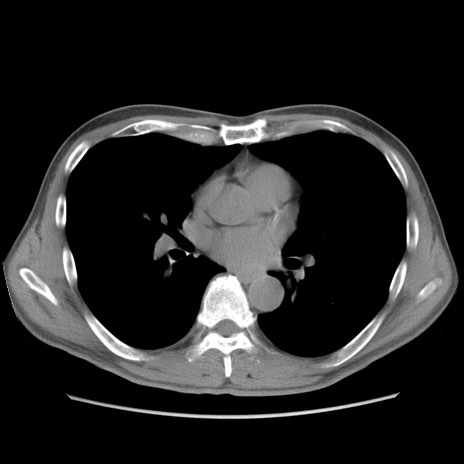

症例56 CT(横断像)

脂肪ウインドウ